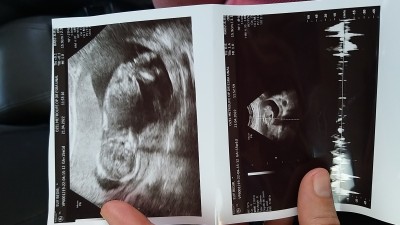

15 + 1 günlük gebeliyim doktor kız dedi bebeğe değişme ihtimalli  var mı kesinlikle ayrım yaptığımdan değil-dir

Gebelik haftası 15+1 gebelik

Benimkide ilk defa yorum yaptı kız dedi ultrason kağıdını attım zaten arkasını dönmüştü yüz üstü yatmış:) bakalım değişecek mi

Gösteriyorsa ilk zamanlar kız diyorlar benim tosbik de kız ve göstermedi 15+3 e kadar hiç :) suan bile saklıyor veya bacak arasını kapatıyor görmek zor oluyor :)

20 ye kadar kızdan emin olamıyorlar bazen pipisini saklıyor bebişler ya da doktor kordon zannediyor ama bazen de kordonu pipi sanıyorlar o da ayrı hayırlı evlat olsun inşallah :)